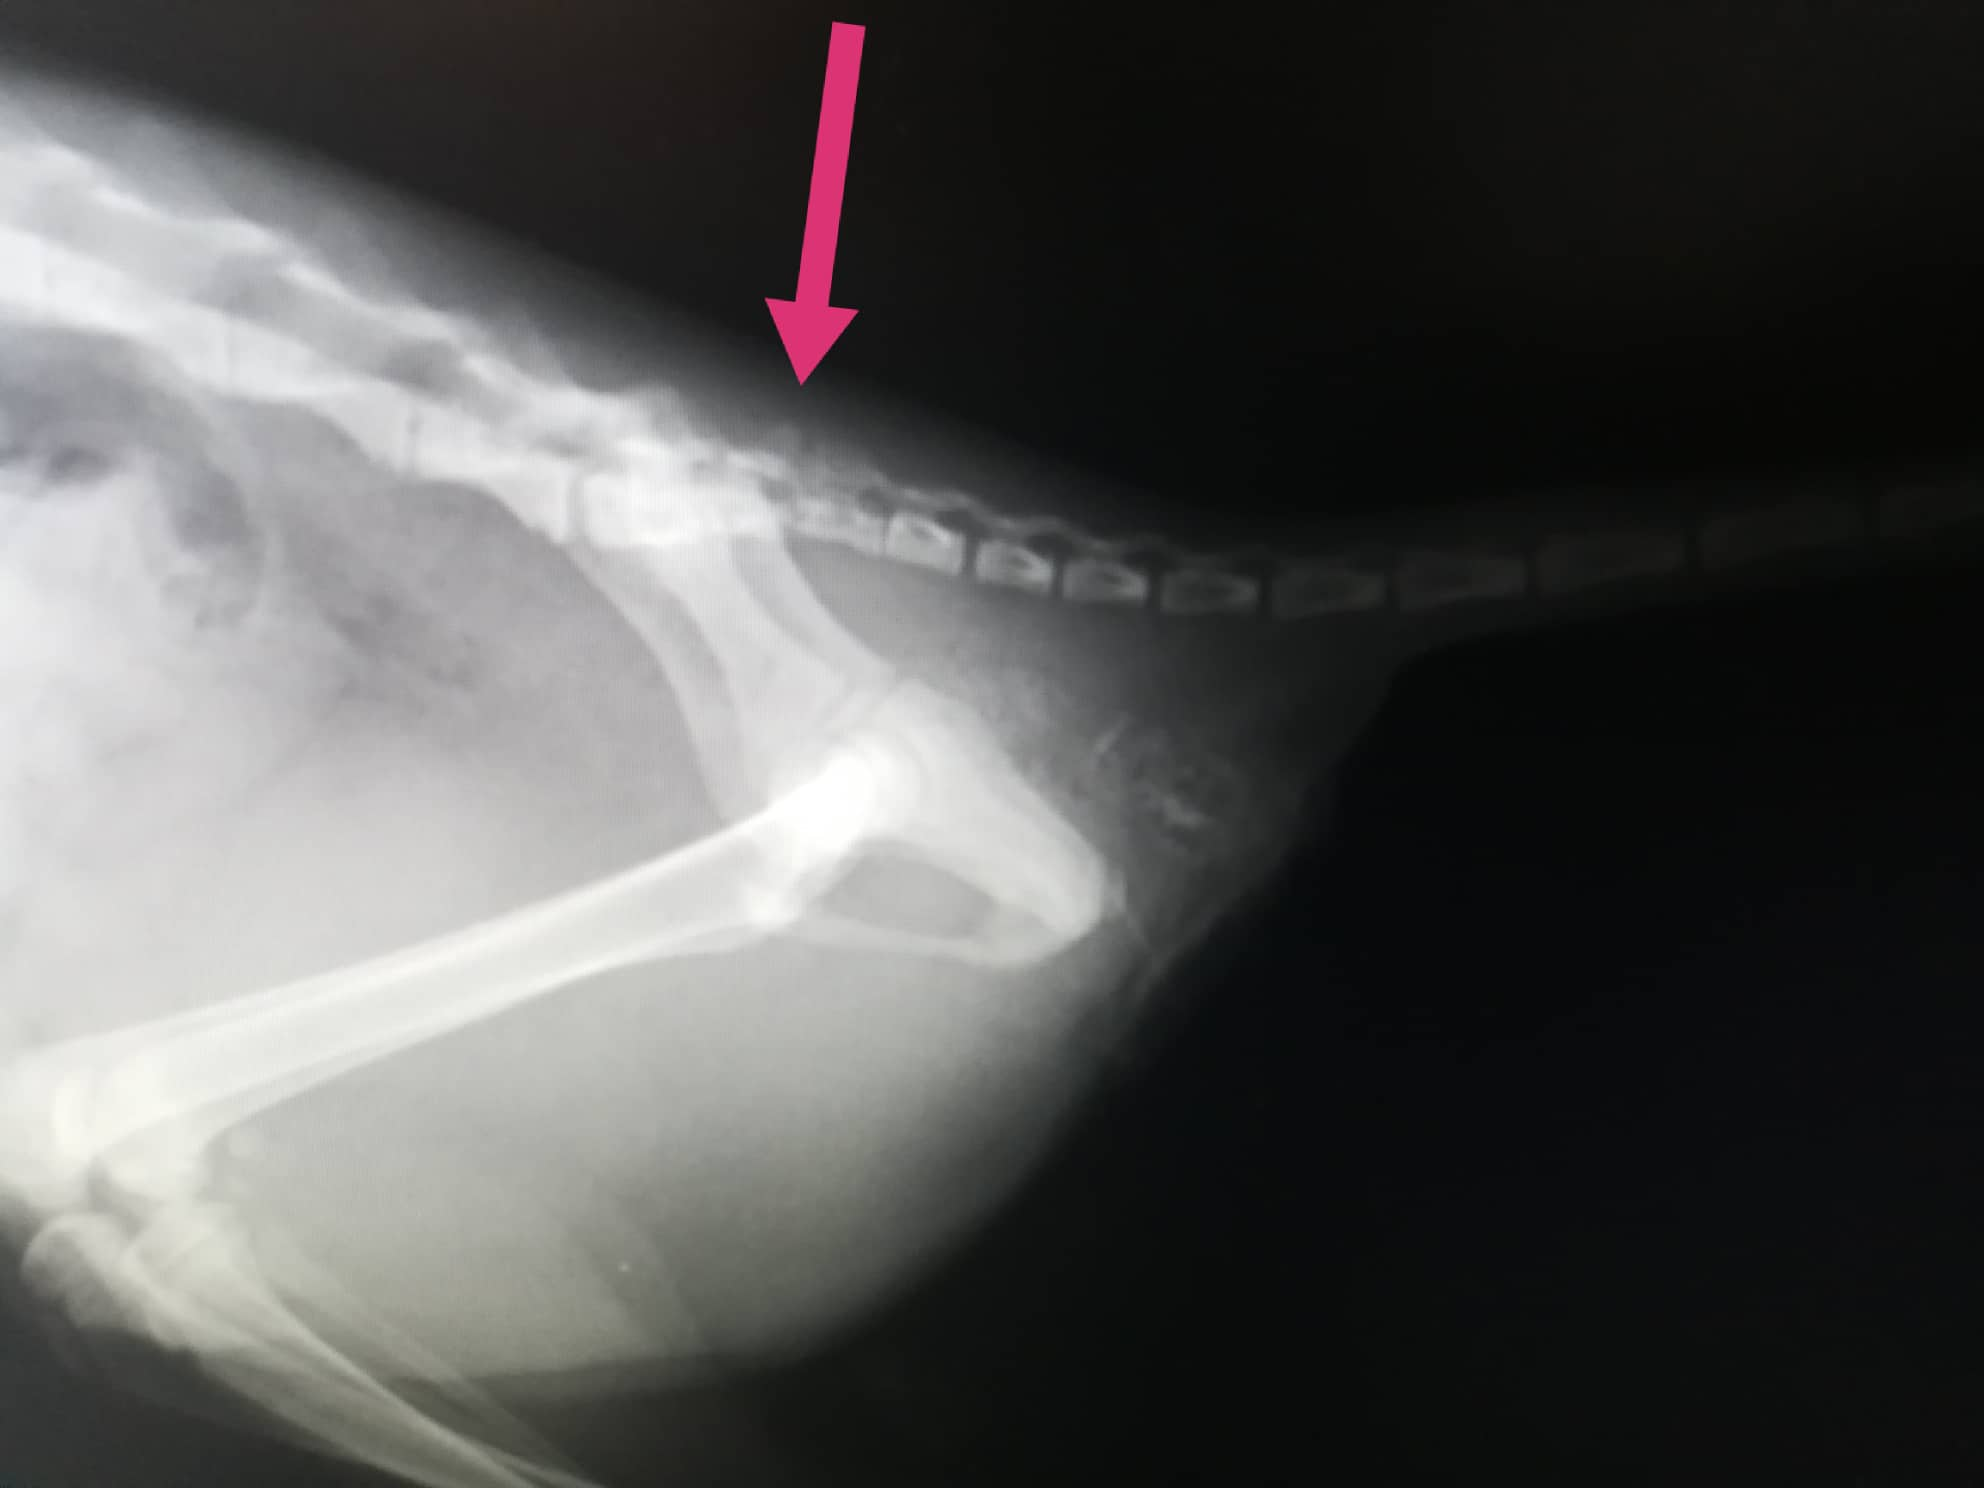

Kočička špatně chodí na zadní nohy, je inkontinentní, neudrží stolici, čůrala krev a má nefunkční ocásek, u kterého se zvažovala jeho amputace.